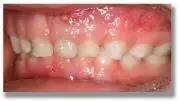

宝宝的牙齿是这样的,他吃饭慢,是正常的吗?

葉子张野 博士

看看这深咬合关系,能吃快才怪。

深咬合的影响也是很大的,比如会影响颜值,影响咀嚼功能,引起颌关节疾病、偏头痛、耳鸣、牙周病、咬合创伤等、甚至还会影响发音和导致心理疾病。

深咬合,早期矫正才是王道!